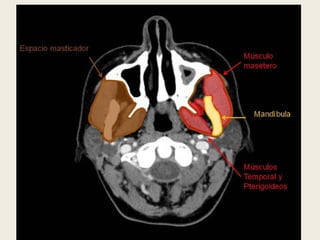

ESPACIO MASTICADOR.

Situado anteriormente al espacio parafaríngeo,

está rodeado por la fascia cervical profunda, que

se divide en 2 capas a este nivel. Se encuentra en

la fosa infratemporal y contiene los músculos de

la masticación (masetero, temporal, pterigoideo

medial y lateral), la rama vertical y cuerpo de la

mandíbula, los nervios mandibular y alveolar

inferior (ramas de la tercera rama del nervio

trigémino) y la vena y arteria alveolar inferior.